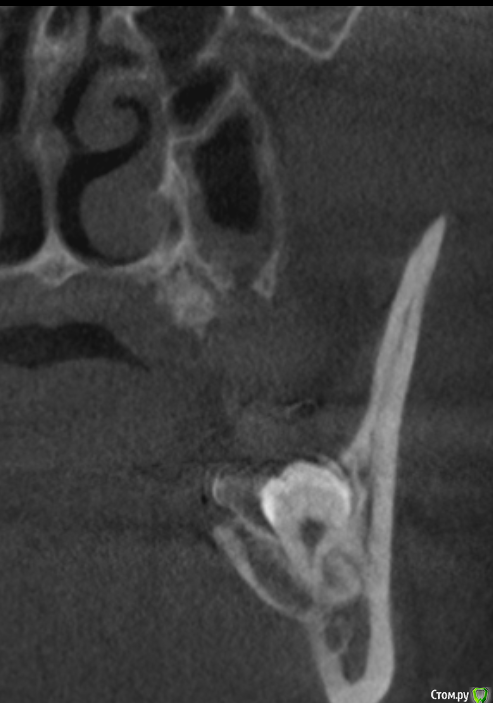

It'sGeorgy Опубликовано 30 ноября, 2019 Поделиться Опубликовано 30 ноября, 2019 Всем доброго времени суток! Пациентке в сторонней клиники 1.5 года назад удаляли 2.8 зуб. Удаление заняло больше часа. После этого, с ее слов был гайморит, который пол года не могли вылечить т.к. не могли найти причину. На срезах(кт не могу прикрепить к сожалению сейчас):1 - Пазуха + сообщение2 - Состояние лунки3 - Недоудаленный корень в области 2.7 зуба(?) На слизистой ОАС не нашел. На данный момент активных жалоб нет, но порой "Побаливает". - Стоит ли лезть и пытаться закрывать сообщение? Какова методика операции и где можно про нее почитать?(До этого закрывал только ОАС с выходом на слизистую с помощью лоскута со щеки + ССТ) Или просто передать ЛОРу на удаление полипов из пазухи? - Стоит ли лезть и пытаться удалять корень или пусть там полежит? Ссылка на комментарий

It'sGeorgy Опубликовано 4 декабря, 2019 Автор Поделиться Опубликовано 4 декабря, 2019 тогда что Вы собрались закрывать???На КТ видно, что лунка не зарастает костной тканью из нее есть сообщение с пазухой. Прошло уже 1.5 года. Вопрос в том, нуждается ли это в лечении и где можно почитать про ведение таких случаев. Ссылка на комментарий

___49___ Опубликовано 4 декабря, 2019 Поделиться Опубликовано 4 декабря, 2019 (изменено) На КТ видно, что лунка не зарастает костной тканью из нее есть сообщение с пазухой. То , что костной ткани нет - видно. Не зарастает , но при этом нет ороонтрального сообщения - это как ? Если вы считаете, что наличие кости между полостью рта и пазухой обязательно , то это не так, недавно закрыл ороонтральное сообщение которому более 10 лет , при этом костный дефект(костное окно) между полостью рта и пазухой примерно 8 *8 мм. через 1.5 месяца ротоносовая проба отрицательна , пазуха чистая, костное окно без изменений и так скорее всего и останется , считаю пациентку выздоровевшей . В вашем случае наблюдал бы пациентку в динамике, показаний к травматичным операциям на данный момент нет , вероятность того, что апекс там проживет всю жизнь( так как полная ретенция вы писали и надеюсь без альвеолита ) и более не проявит себя, вполне имеет место быть . Изменено 4 декабря, 2019 пользователем ___49___ 2 Ссылка на комментарий